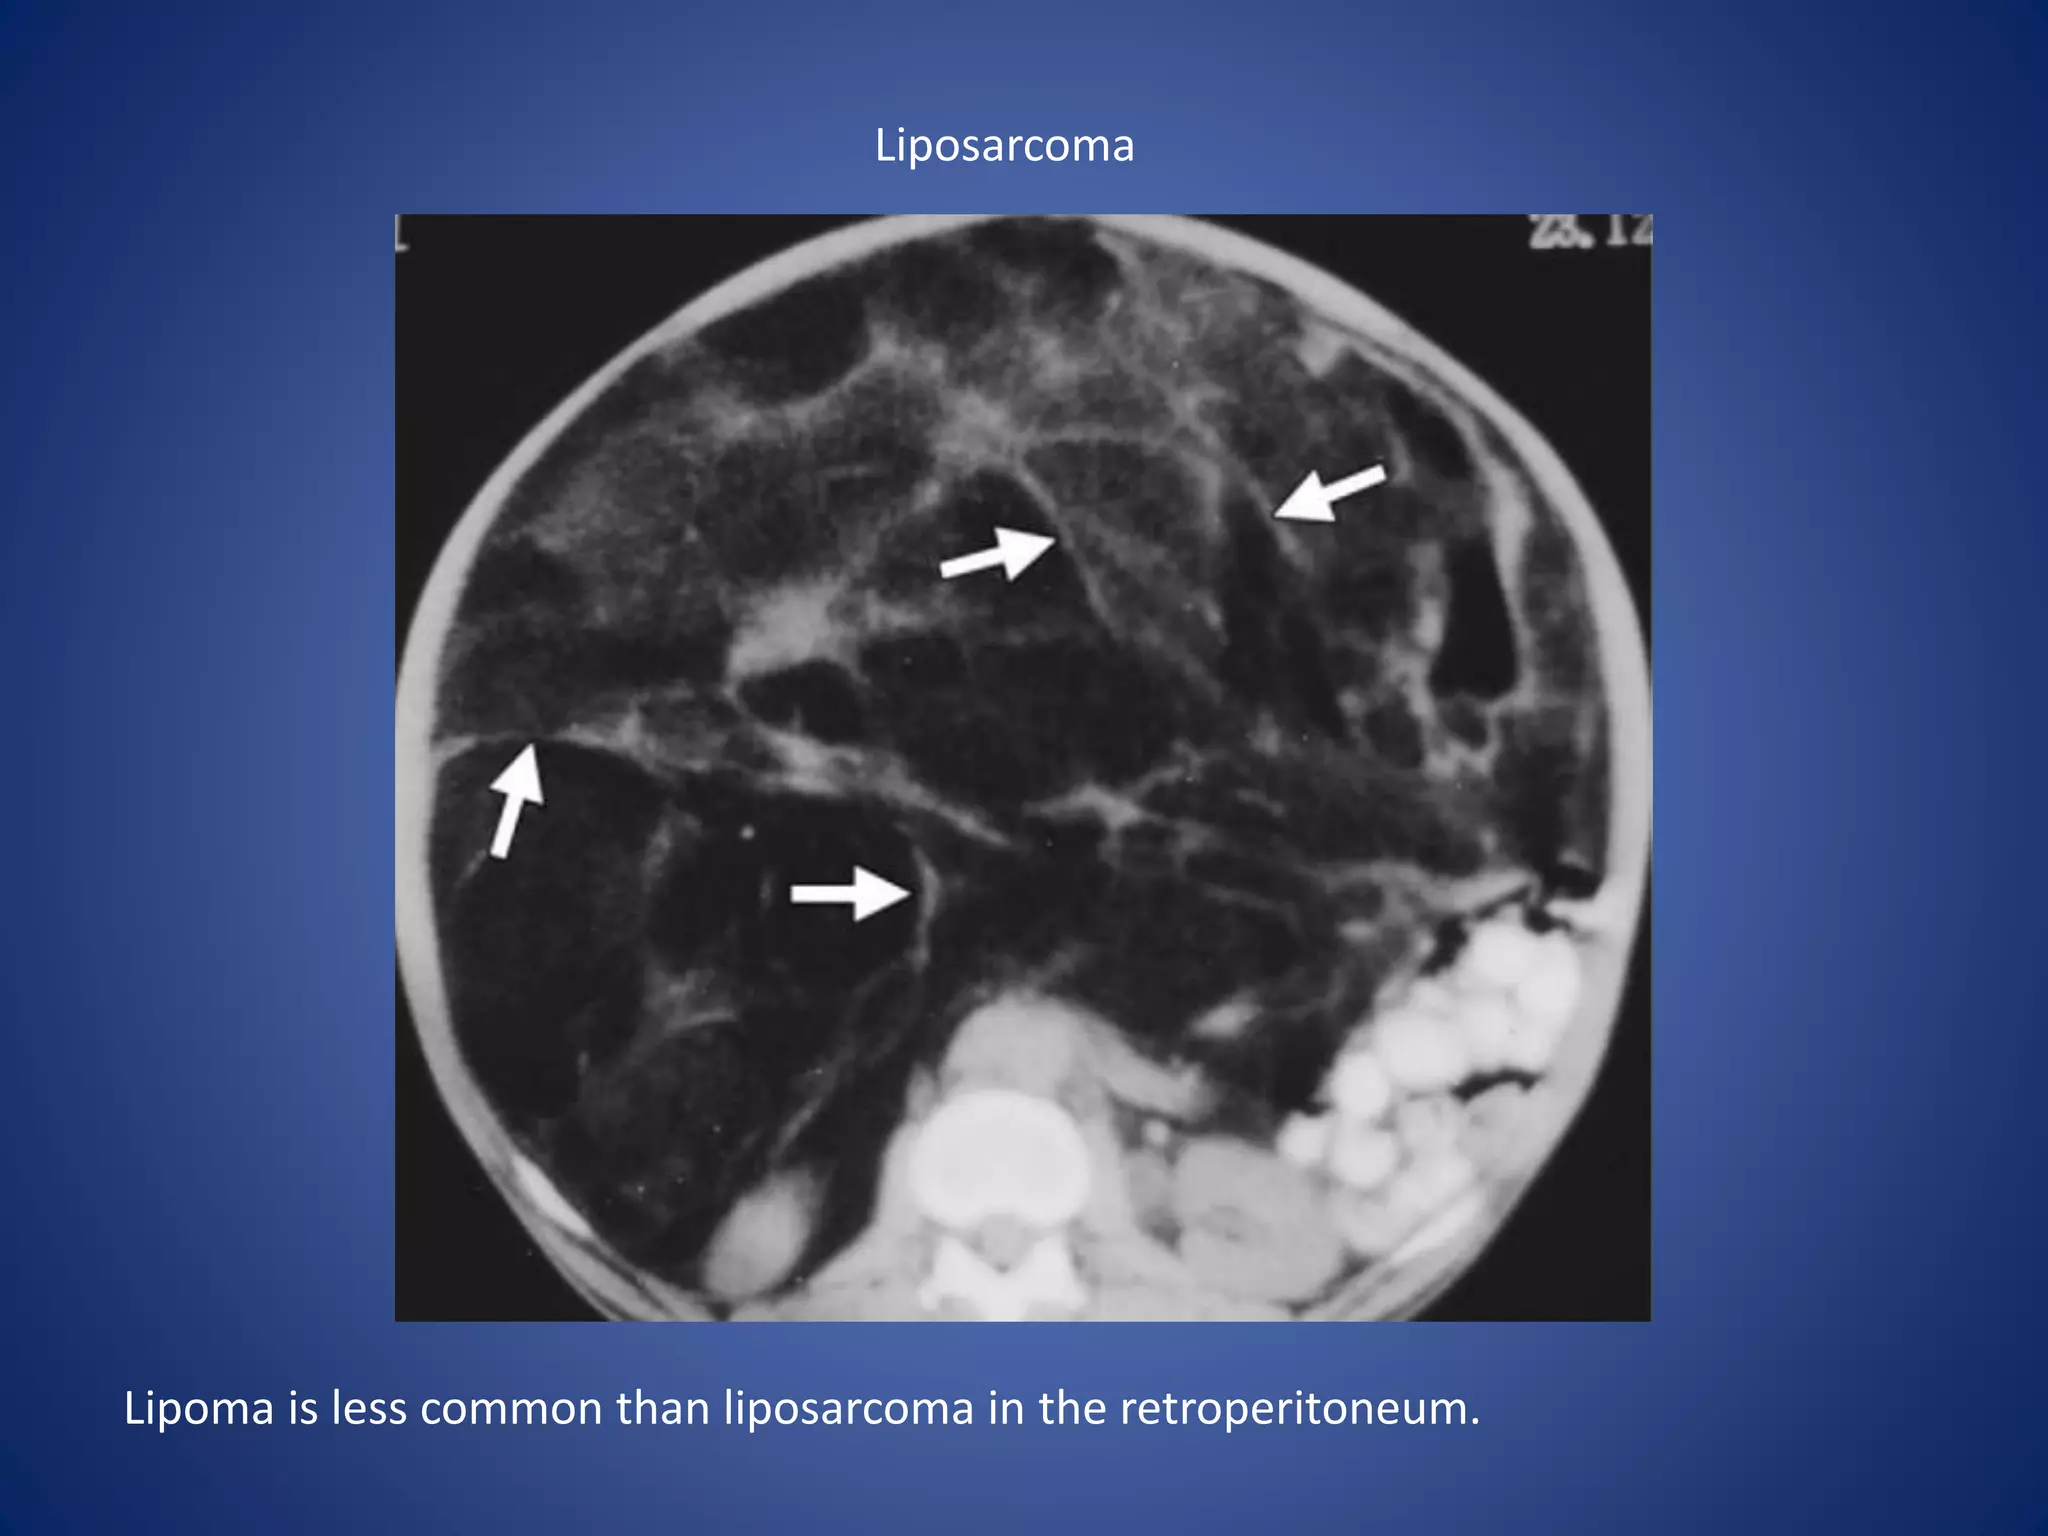

Liposarcoma

Lipoma is less common than liposarcoma in the retroperitoneum.

The appearance of liposarcoma may be similar to that of a lipoma,

but liposarcoma has thicker, irregular, and nodular septa that show

enhancement after contrast material administration.

• #73 Liposarcoma --- Large retroperitoneal mass predominantly of fatty attenutation with irregular nodular septations The appearance of liposarcoma may be similar to that of a lipoma, but liposarcoma has thicker, irregular, and nodular septa that show enhancement after contrast material administration.